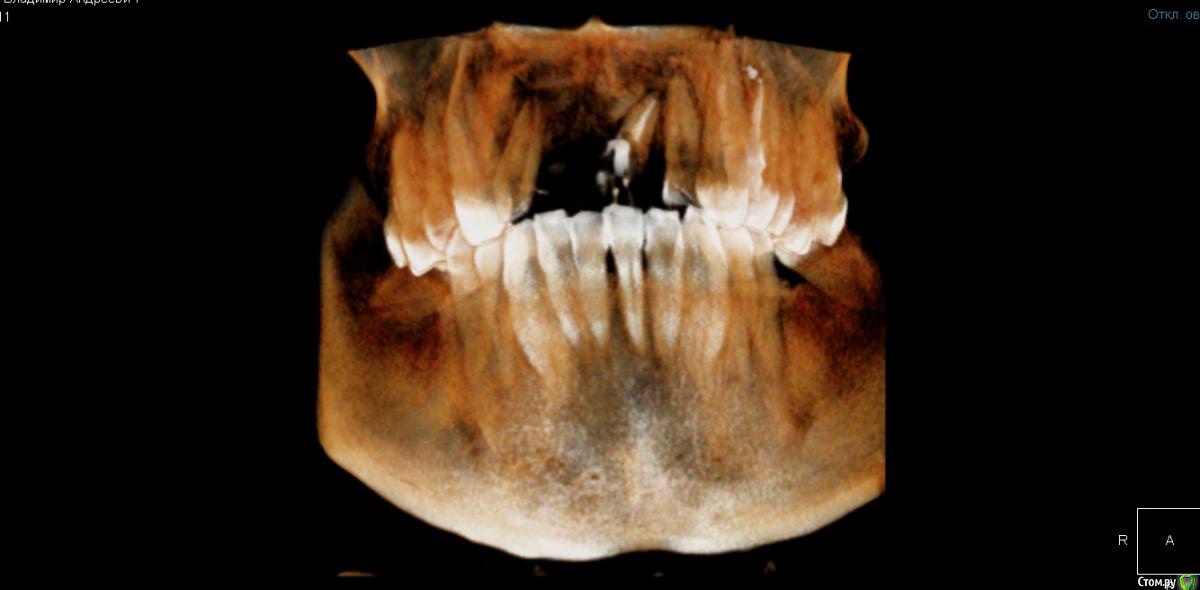

Владимир Андреевич Опубликовано 6 декабря, 2019 Поделиться Опубликовано 6 декабря, 2019 Здравствуйте! Помогите, пожалуйста, советом.Ситуация такая - нет нижних жевательных с обоих сторон...нет уже давно, верхние зубы выдвинулись в сторонуотсутствующих. Сейчас есть возможность заняться зубами, поставить импланты, но под них банально нет места(С одной стороны всё более-менее, место нашли, а вот с другой стороны совсем беда, причем там еще и сверху одного зубанет (и один сильно стерся, но он еще пригоден для протезирования), соответственно нижние выдвинулись в сторону верхних, отсутствующих.Ортопед говорит, что ортодонтия тут не поможет (вот вообще никак!), предложил ставить огромную дугу, с 6ки до 6ки, но мне такой план совсем не по нраву...Помогите, пожалуйста! Можно ли что-то сделать в таком случае, чтобы хоть немного места освободить (потом, возможно, подпилить те зубы, которые мешают)?34 года Ссылка на комментарий

Владимир Андреевич Опубликовано 6 декабря, 2019 Автор Поделиться Опубликовано 6 декабря, 2019 Такой вот еще есть Ссылка на комментарий